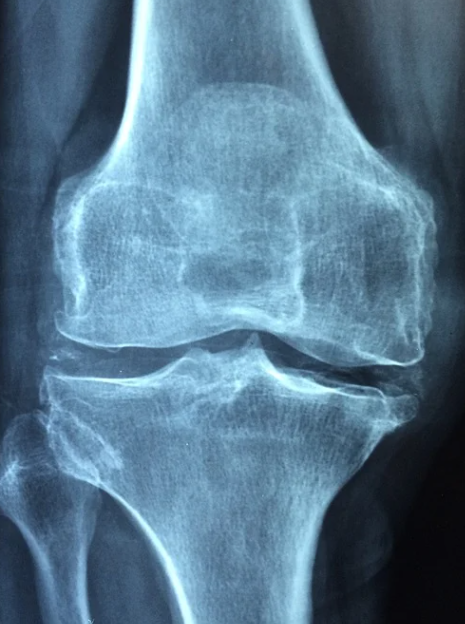

무릎 연골 관절에는 허벅지뼈와 정강이뼈가 맞닿아있다고 한다. 이들의 뼈 끝에 있는 골연골은 뼈가 서로 부딪히면서 손상이 되지 않도록 하는 역할을 하게 되는데, 우리가 무릎에 무리를 줄 수 있는 행동이나 운동을 반복하게되면 뼈를 감싸고 있는 연골이 손상되기 때문에 평소에 무릎이 자주 아프다면 아래에서 언급하는 무릎 연골 손상 대표적 증상 TOP 6에 대해서 알아보고 자신이 해당하는지 파악해보기 바란다.

무릎 연골 손상 대표적 증상들

여기에 언급된 증상들이 100% 정담은 아니지만, 대표적 증상들이며, 이 증상 이외에도 개인적인 증상은 다를 수 있으므로 병원에 방문해서 정확하게 진단을 받는 것이 가장 올바른 진단 방법이라는 것을 항상 인지하자.

무릎 연골이 손상되면 무릎을 내가 구부렸다가 펼 때 무언가 걸리는 느낌이 들거나 무릎이 완벽히 펴지거나 굽혀지지 않는 증상이 나타난다.

무릎 연골의 손상으로 인해서 무릎 앞부분에서 통증을 느끼는 경우도 있다. 일반적으로는 같은 자세로 오랜시간 있다가 일어날 때, 장시간 운전하거나 일을 한 후에 무릎통증이 느껴진다면 이 때는 무릎 연골 손상을 의심해 볼 수 있다.

갑자기 무릎의 힘이 빠져나가서 주저앉게 된다거나, 힘이 빠지면서 넘어질 뻔 했다면 연골 손상이 있는 상태라고 할 수 있다. 혹여 무릎이 부어오르는 증상이 나타난다면 연골의 손상이 심해졌거나 염증이 오랜시간 진행된 상태일 가능성도 고려해보아야 한다.

무릎 연골이 손상되었을 때 가장 힘든 것 중 하나가 바로 어딘가를 오르내리는 일이라고 생각한다.

계단을 오르내릴 때, 등산할 때, 바닥에 앉아있다가 일어날 때, 양반다리를 할 때도 무릎에서 통증이 느껴진다면 이미 무릎 연골이 손상되었다고 생각해볼 수 있다.

무릎 연골 손상의 초기증상이라고 할 수 있는 증상인 시큰거리는 증상. 혹은 가벼운 통증이 느껴질 때가 있다.

하지만 이는 잠깐 쉬거나 무릎 관절을 사용하지 않으면 다시 괜찮아지기 때문에 무릎의 연골이 손상되었다는 생각이 이 때는 들지 않고 컨디션이 좋지 않다고만 생각할 수도 있다.

무릎 연골이 심각하게 손상이 된 경우에는 가만히 있는데도 무릎이 아픈 통증이 발생할 수 있으며, 보행시에 통증이 심해져서 결국은 걷기도 힘들어지는 수준이 된다.